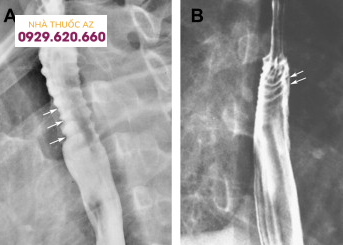

Đối với hẹp thực quản, theo một nghiên cứu được thực hiện trên bệnh nhân thực quản do bạch cầu ái toan, tỉ lệ phát hiện được hẹp bằng chụp Baryt lên đến 71% trong đó chủ yếu là hẹp ở đoạn dưới thực quản. Một nghiên cứu khác ghi nhận đoạn hẹp chủ yếu nằm ở phía trên hoặc thực quản đoạn ngực.

Hình 8: Hình ảnh hẹp thực quản do viêm thực quản bạch cầu ái toan (Nguồn: learningradiology.com)

Hình 9: Hẹp lan tỏa, co thắt thực quản và vòng tròn đồng tâm (Nguồn: radiologykey.com)

Đường kính của đoạn hẹp trung bình khoảng 1cm và vị trí hẹp ở phía đoạn thực quản trên/giữa có xu hướng dài hơn so với đoạn dưới. Tùy vị trí đoạn hẹp trên chụp Baryt vẫn cần cân nhắc đến các chẩn đoán phân biệt khác. Các nguyên nhân khác gây hẹp ở đoạn thực quản trên hoặc giữa bao gồm thực quản Barrett, xạ trị vùng trung thất, sử dụng một số loại thuốc như NSAID, quinidine, trong khi hẹp ở đoạn dưới thực quản có thể do viêmthực quản trào ngược. Cần chú ý những bệnh nhân có hình ảnh hẹp thực quản trên chụp Baryt thường có triệu chứng nuốt khó và đây chỉ là một dấu hiệu gợi ý, cần kết hợp nhiều yếu tố liên quan đến bệnh sử, triệu chứng lâm sàng, hình ảnh nội soi và mô bệnh học.Vòng thực quản cũng là hình ảnh hay gặp với nhiều thuật ngữ được sử dụng như “khí quản hóa thực quản” hay “thực quản dạng vòng”. Vị trí và sự phân bố của các vòng thực quản rất khác nhau trên nội soi, có thể ở các đoạn của thực quản hoặc phân bổ lan tỏa nhiều chỗ. Đôi khi những vòng này có thể gây hẹp khiến dây sợi khó đưa qua được. Trên chụp Baryt, các vòng này thường nhiều, hay xuất hiện gần nhau, có dạng đồng tâm dọc theo lòng thực quản.